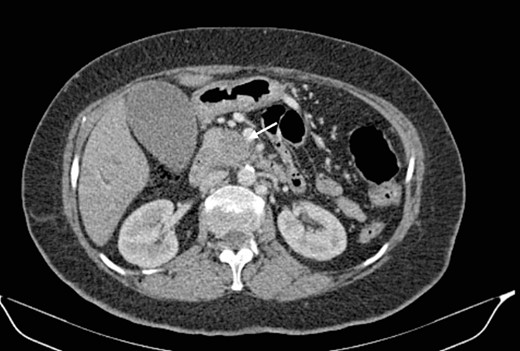

Mr. A. is a 65-year-old hypertensive patient presenting with acute epigastric pain associated with abdominal bloating. Biological settings showed amylasemia at 450 IU/L and lipasemia at 525 IU/L. Abdominal CT scan revealed heterogenous poorly defined mass in the pancreatic head with low enhancement (Figs 1 and 2). The CA 19–9 assay was 280 IU/L. Cephalic duodenopancreatectomy was performed. Histological examination of the operative specimen revealed a solid, trabecular, undifferentiated carcinomatous process (Fig. 3) expressing markers (CK(AE1-AE3) and p40) (Fig. 4), confirming the diagnosis of primary squamous cell carcinoma of the pancreas. The extension study showed no secondary localization.

Low-enhancing poorly defined mass in the pancreatic head with surrounding fat stranding (arrow).